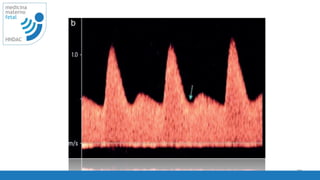

Doppler espectral

cambio de velocidad del flujo

respecto al tiempo